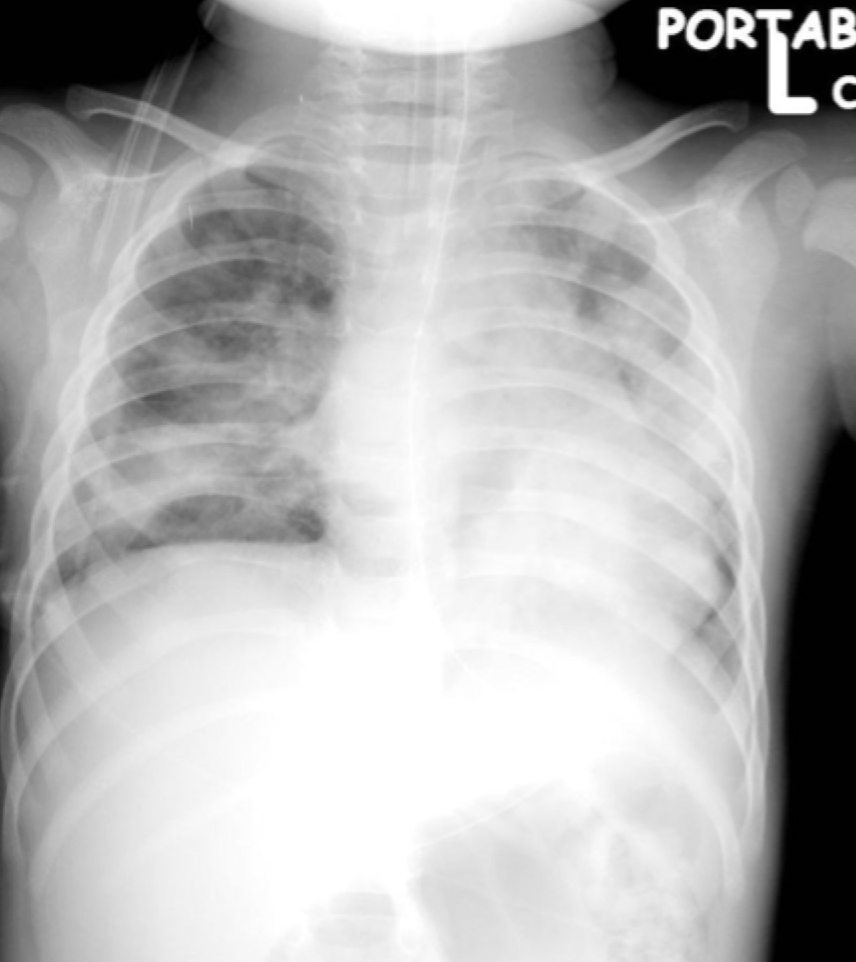

4

Q

?

A

Tension pneumothorax:

-Large amount of air in the affected hemithorax and CONTRALATERAL shift of the mediastinum